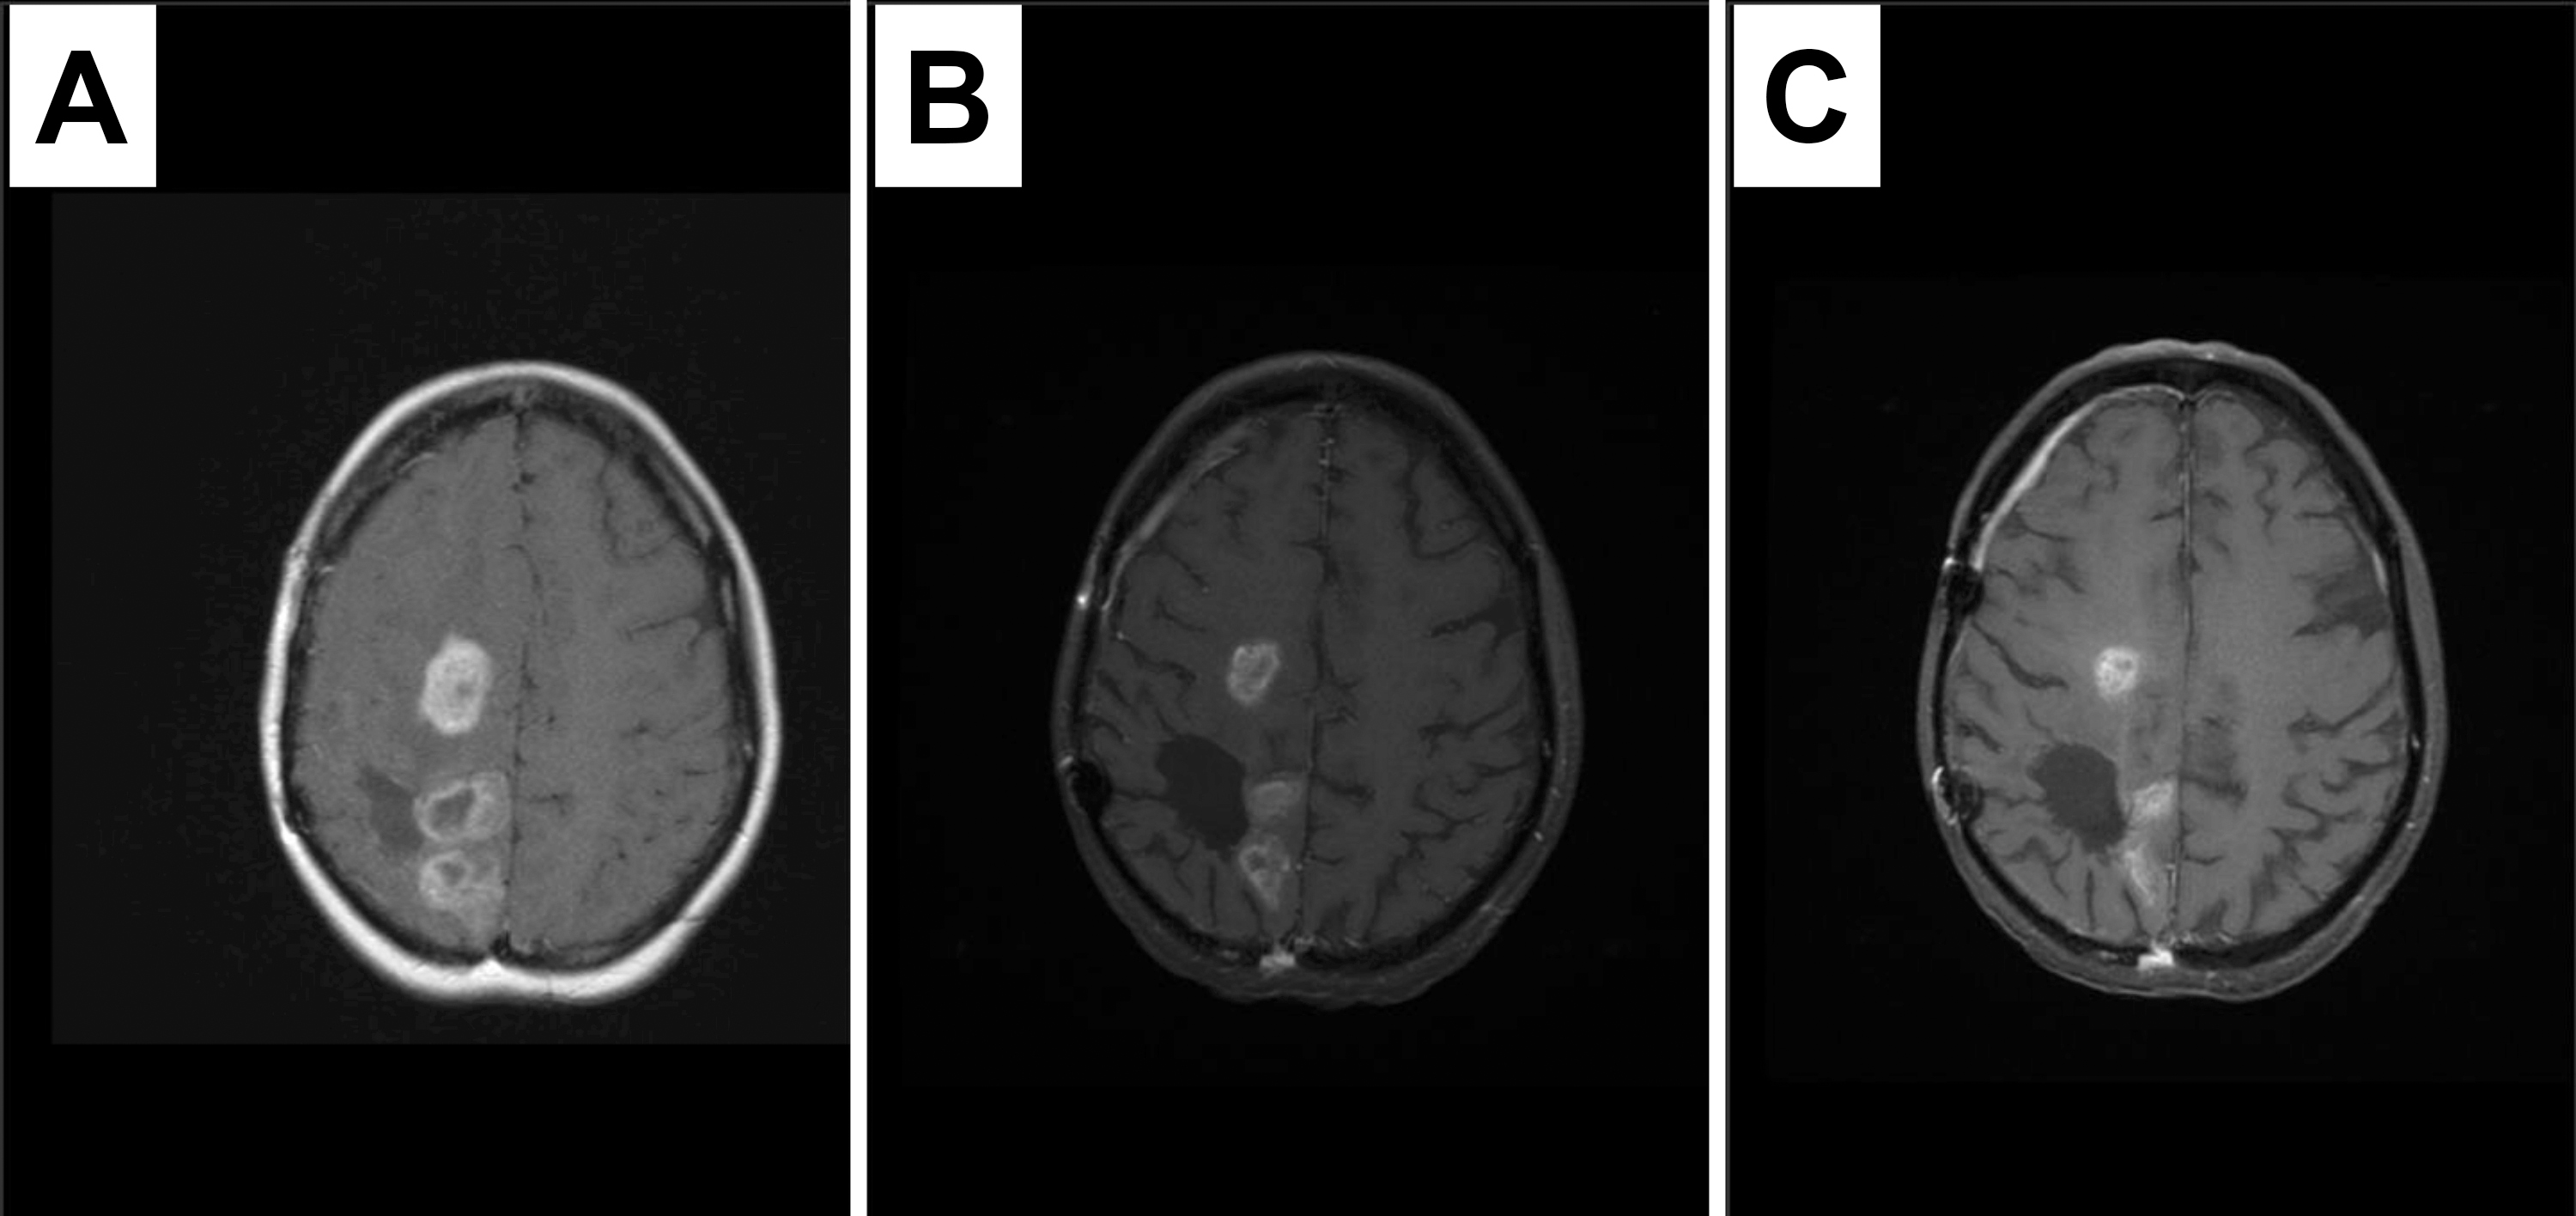

The rapid return of testing results was considered feasible, as results were returned within the 14-day study target goal in 90% of subjects (n = 18/20). Median time to return of results was 11.5 days (range 6–22 days). Only seven study subjects (35%) had tissue available at the primary study institution, and tissue was obtained from an outside institution for the remaining 13 subjects (65%). Testing was returned for the two subjects who did not meet the 14-day study target goal at 19 and 22 days. The delay to testing results was due to time to obtain tissue from outside institution in both cases. Targeted sequencing was performed for 18 subjects (90%), and oncogenic mutations or copy number changes were found in 15 of 18 tested (83%). Details of patient characteristics, prior treatment, and testing results are provided in Table 1. The highest levels of protein overexpression (3–4+) were often observed to be associated with gene amplifications or pathway mutations (Fig. 2). In six cases, 33% of cases sequenced, the immunohistochemical staining results identified cases with genetic alterations predicted to respond to targeted drug therapy.

Fig. 2.Examples of high immune positivity associated with gene amplification, subject 3. (A) PDGFRA overexpression associated with gene amplification; subject 7 (B) EGFR overexpression associated with gene amplification; subject 14 (C) pS6 overexpression associated with TSC2 mutation.